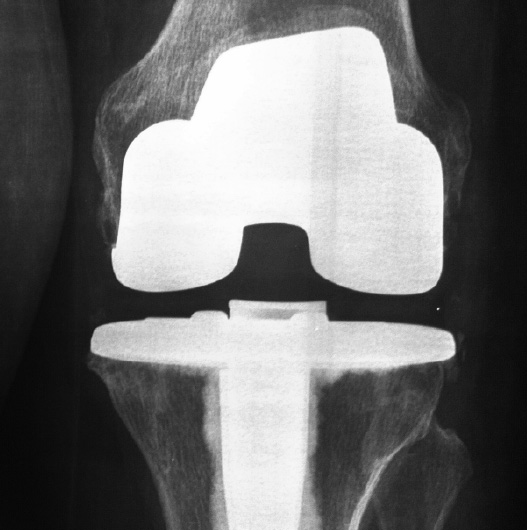

PRÓTESIS TOTAL

El reemplazo articular protésico de la rodilla consiste en el recambio de las superficies articulares del fémur, tibia y patela desgastadas y sin cartílago, por componentes metálicos que recrean la superficie de la articulación (tienen la misma forma) así como también la colocación de un espaciador de polietileno que permite crear una superficie de deslizamiento suave.